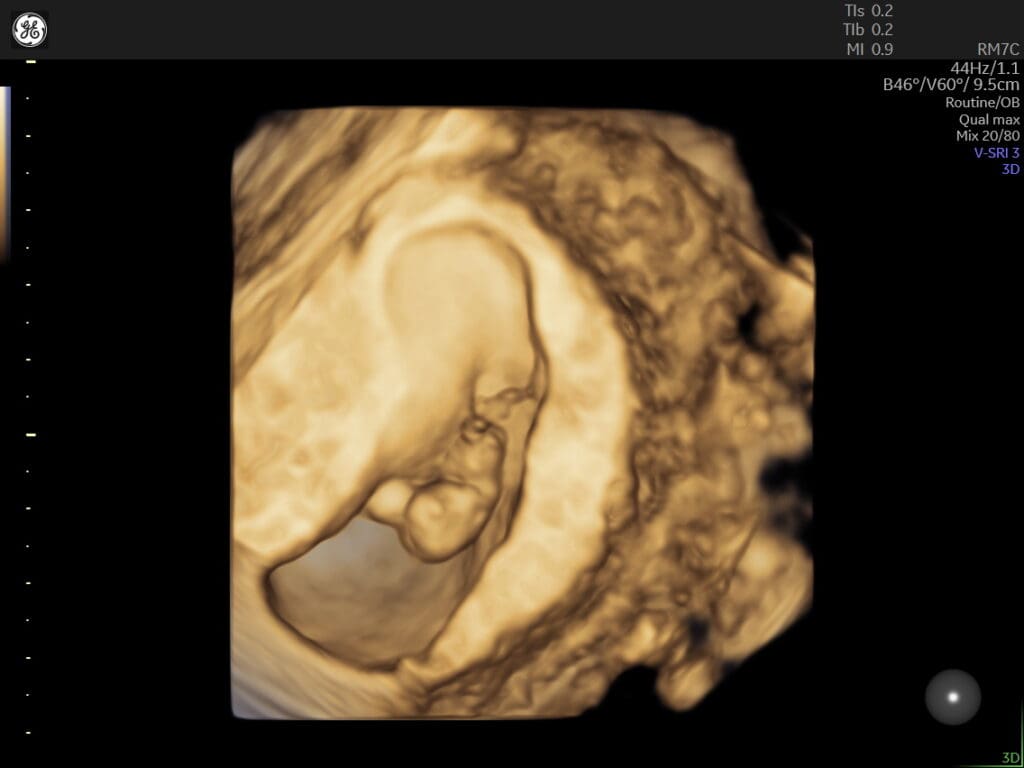

The viability scan is usually conducted between 6 to 10 weeks of gestation. It aims to confirm the presence of a gestational sac, which is a fluid-filled structure where the baby develops, and to detect the baby’s heartbeat. This scan helps determine if the pregnancy is progressing as expected and if the baby is growing properly.

During the scan, a healthcare professional will use an ultrasound machine to carefully examine the uterus and the gestational sac. They will look for the presence of a yolk sac, which provides nourishment to the developing embryo, as well as the fetal pole, which contains the early stages of the baby’s body.

The detection of a heartbeat is a significant milestone in the viability scan. It indicates that the baby’s heart has started beating, which is a reassuring sign of a healthy pregnancy. Additionally, the scan may also provide an estimated gestational age, which helps in determining the due date and tracking the progress of the pregnancy.